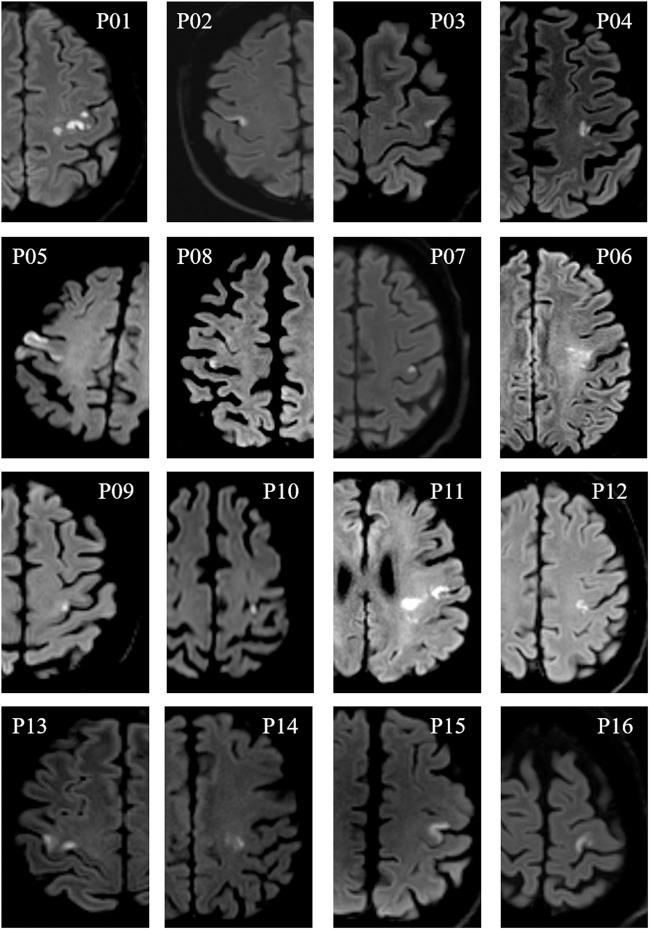

After stroke restricted to the primary motor cortex (M1), it is uncertain whether network reorganization associated with recovery involves the periinfarct or more remote regions. We studied 16 patients with focal M1 stroke and hand paresis. Motor function and resting-state MRI functional connectivity (FC) were assessed at three time points: acute (<10 days), early subacute (3 weeks), and late subacute (3 months). FC correlates of recovery were investigated at three spatial scales, (i) ipsilesional non-infarcted M1, (ii) core motor network (M1, premotor cortex (PMC), supplementary motor area (SMA), and primary somatosensory cortex), and (iii) extended motor network including all regions structurally connected to the upper limb representation of M1. Hand dexterity was impaired only in the acute phase ( = 0.036). At a small spatial scale, clinical recovery was more frequently associated with connections involving ipsilesional non-infarcted M1 (Odds Ratio = 6.29; 0.036). At a larger scale, recovery correlated with increased FC strength in the core network compared to the extended motor network (rho = 0.71; = 0.006). These results suggest that FC changes associated with motor improvement involve the perilesional M1 and do not extend beyond the core motor network. Core motor regions, and more specifically ipsilesional non-infarcted M1, could hence become primary targets for restorative therapies.

在局限于初级运动皮层(M1)的中风后,与恢复相关的网络重组是否涉及梗死周边或更远的区域尚不确定。我们研究了 16 名患有局灶性 M1 中风和手部无力的患者。在三个时间点评估了运动功能和静息状态 MRI 功能连接(FC):急性(<10 天)、早期亚急性(3 周)和晚期亚急性(3 个月)。在三个空间尺度上研究了 FC 与恢复的相关性,(i)同侧未梗死的 M1,(ii)核心运动网络(M1、运动前皮层(PMC)、辅助运动区(SMA)和初级体感皮层),以及(iii)包括与 M1 的上肢代表结构连接的所有区域的扩展运动网络。手部灵巧性仅在急性期受损(=0.036)。在小空间尺度上,临床恢复更频繁地与涉及同侧未梗死 M1 的连接相关(优势比=6.29;=0.036)。在更大的尺度上,与扩展运动网络相比,核心网络中 FC 强度的增加与恢复相关(rho=0.71;=0.006)。这些结果表明,与运动改善相关的 FC 变化涉及梗死周边的 M1,并且不会超出核心运动网络。因此,核心运动区域,特别是同侧未梗死的 M1,可能成为恢复治疗的主要目标。